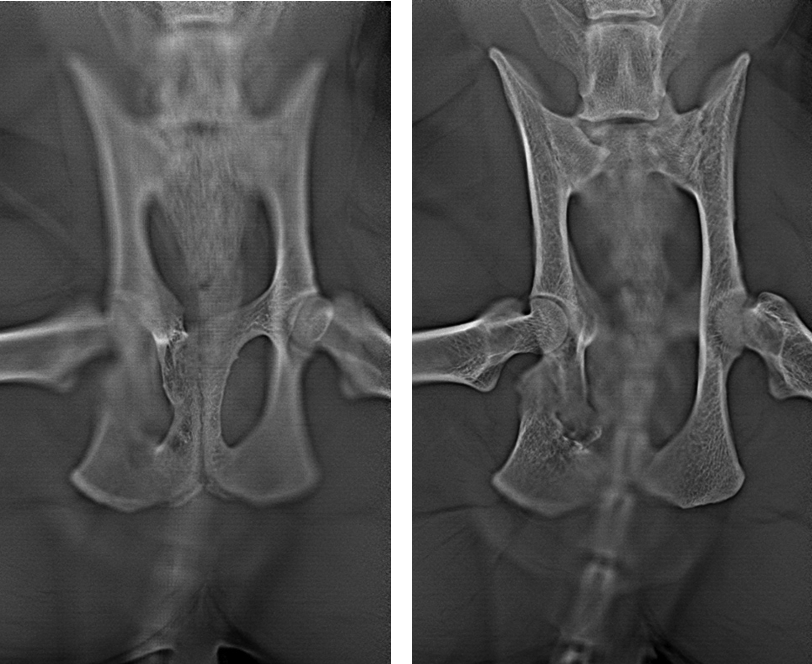

In one study reporting TPO in five cats with obstipation (Cinti et al, 2020), a measure of pelvic canal diameter was employed in pre-operative and postoperative radiographic images to quantify the success of the technique. This measure had been reported previously by Hamilton et al (2009) in a study documenting techniques for pelvic fracture fixation.

The measure is termed the sacral index. The sacral index is the ratio between the width of the sacrum at its cranial border and the distance between the medial acetabular walls made in ventrodorsal radiographic projections of the pelvis (it answers the question, “How wide is the pelvis at the level of the hips compared with at the level of the sacrum?”). Where the sacral index was below 45%, a high risk of obstipation existed (Hamilton et al, 2009).

However, this index is only a two-dimensional measurement, and obstipation will not necessarily follow in every case where the sacral index is below 45%. Consider, for example, a situation in which severe medial and ventral displacement of one hemipelvis is present. The sacral index would suggest significant narrowing of the pelvic canal, but it is possible that a wily rectum might find a way to snake through, without being compressed.

The pelvis is a three-dimensional structure. Two-dimensional imaging is no substitute for checking the pelvic canal diameter through digital per-rectum palpation. However, digital palpation only gives an estimate of the pelvic canal dimensions caudal to the point at which the finger can progress no further.